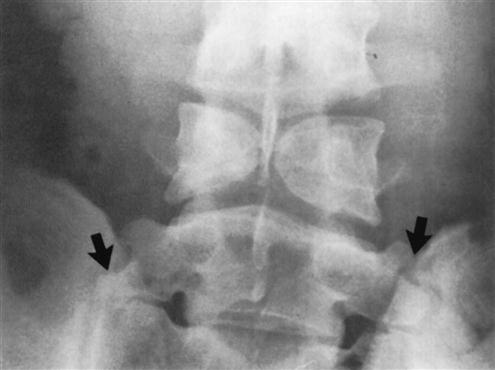

With this view (Figure 9-96), the examiner should note the following:

6. Any evidence of lumbarization of S1, making S1–S2 the first mobile segment rather than L5–S1. Lumbarization occurs in 2% to 8% of the population (Figure 9-104).

7. Any evidence of sacralization of L5, making the L4–L5 level the first mobile segment rather than L5–S1. This anomaly occurs in 3% to 6% of the population (Figure 9-105).

8. Any evidence of spina bifida occulta, which occurs in 6% to 10% of the population (see Figure 9-102).